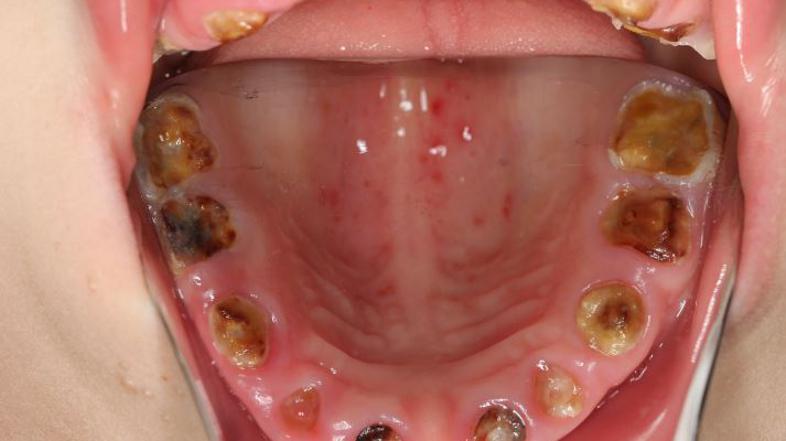

Šele leto in pol staremu otroku so morali izpuliti vse zobe

Gnili zobje UKCLJ

"Imeli smo leto in pol staro deklico, ki smo ji izpulili vse zobe, ki jih je lahko imela takrat v ustih,"  je na novinarski konferenci, kjer so zobozdravniki lani pozvali k prenovi sistema zobozdravstvene preventive dejala Tanja Tomaževič s centra za otroško in preventivno zobozdravstvo na stomatološki kliniki.

Strokovnjakinja je dodala, da je tako majhne otroke zelo težko zdraviti. "Dobimo otroka, ki je star dobro leto, ali v tretjem letu starosti. Ker vemo, da ni sposoben sodelovati z nami, da ne razume, da mu je treba popraviti zobek, ga bi bilo treba prijeti in narediti na silo, česar si ne želimo, sploh če je treba popraviti več zob. Zato že tako majhni potrebujejo poseg in to pri splošni anesteziji,"  je povedala Tomažičeva, ki v teh dneh znova opozarja starše, naj bodo pazljivi kaj pojedo in predvsem pijejo njihovi otroci.

Takšne otroke je zelo težko zdraviti

Po besedah stomatologinje, se sprva na zobeh pokažejo bele lise, ki so posledica izgube mineralov iz sklenine. Če bolezen napreduje, je zob treba zdraviti, pri napredovani bolezni pa mlečne zobe večinoma odstraniti.  Če napreduje v dentin, se zdravi s plombami. Če bolezen napreduje še naprej do pulpe in je razširjena že preko pulpe v kost, je treba tak zob endodontsko zdraviti, mlečnega pa večinoma odstraniti, pojasnjuje in dodaja. "Otrok, ki ima karies, do četrtega, petega leta ne razume, da je obisk zobozdravnika zanj dober. S temi otroki je zelo težko delati, ker jim je težko pojasniti, da bodo dobili lokalno anestezijo “komarčka”, da jih ne bi bolelo, hkrati pa je njihova pozornost zelo kratkotrajna."